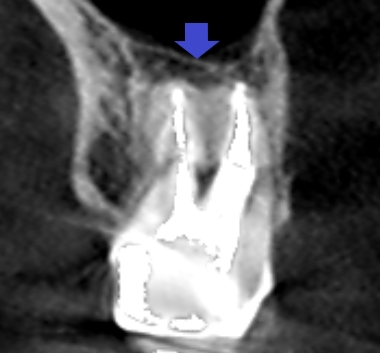

6カ月後の経過観察時の矢状断のCT画像です。矢印の先にあった膿の影が消え、歯槽骨が再生しています。